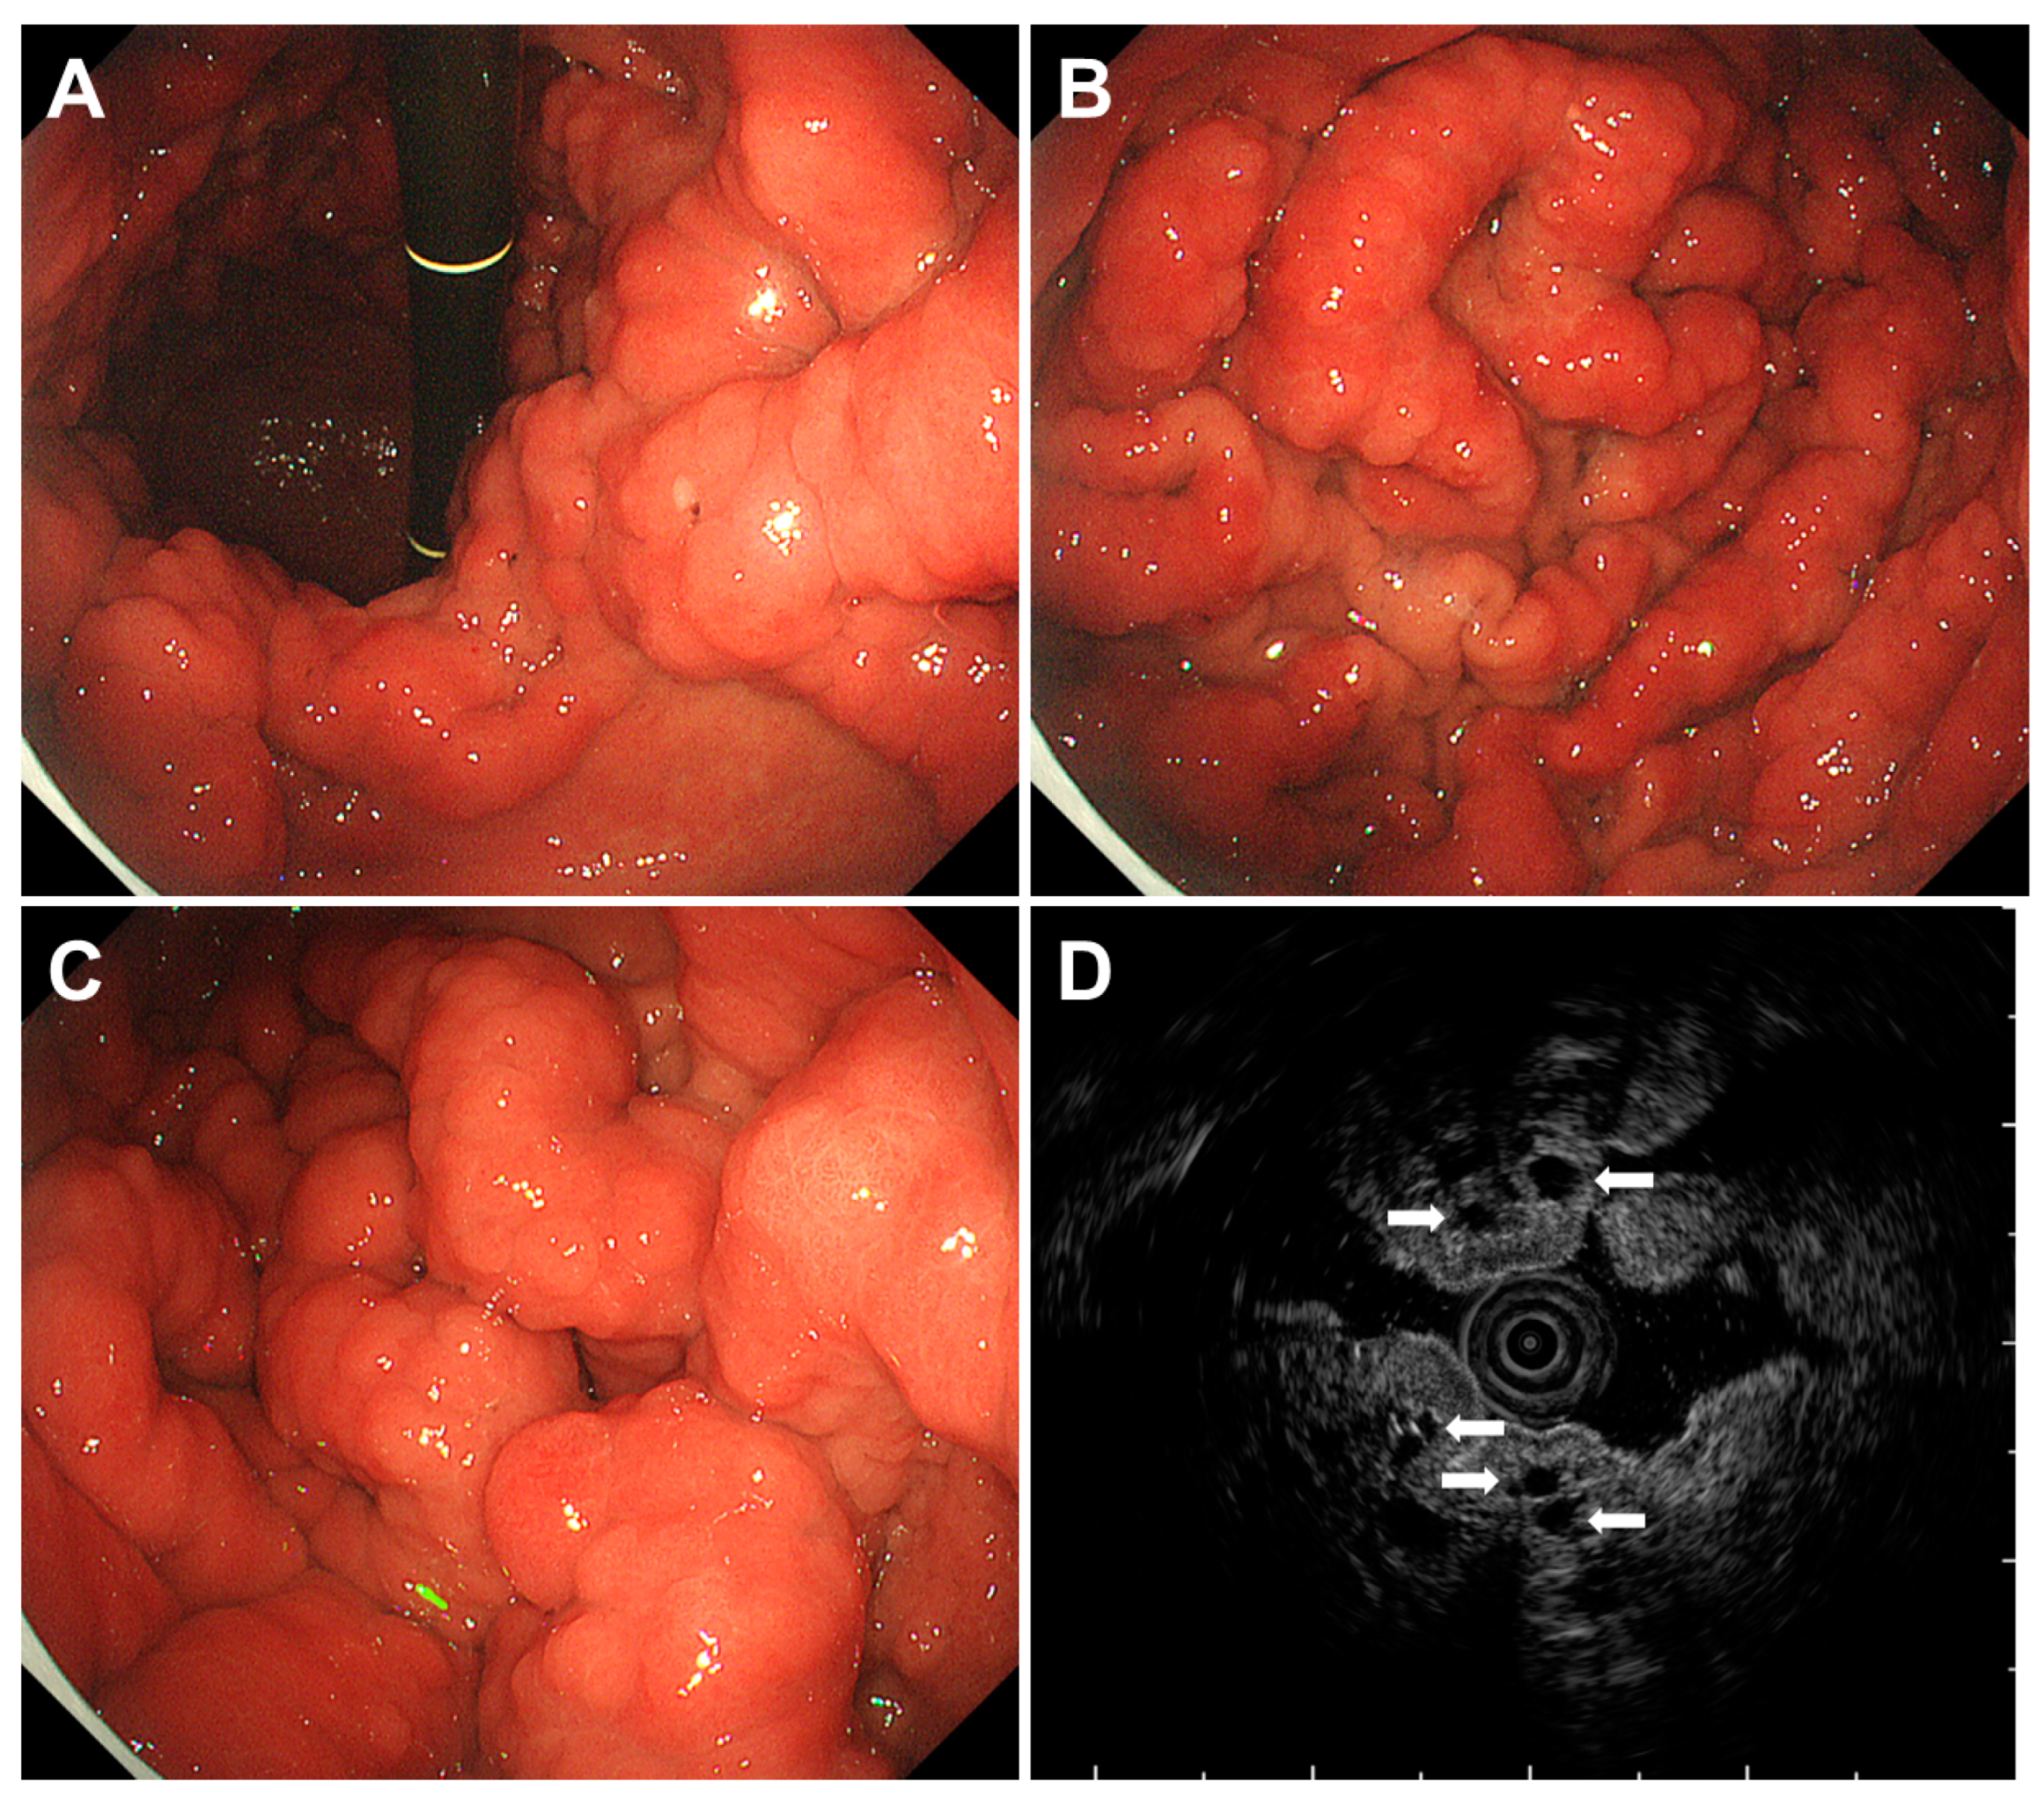

| Cronkhite-Canada syndrome | Not yet elucidated | Gastric polyps ranging from several millimeters to 20 mm in size are observed diffusely as sessile or slightly pedunculated elevations with a dense distribution. Edema with inflammation is present in the intervening mucosa between the polyps. |

| Juvenile polyposis syndrome | Mutations in the SMAD4 or BMPR1A gene | Papillary or tongue-like polyps, multiple and reddish in color of varying sizes with swollen or edematous features. |